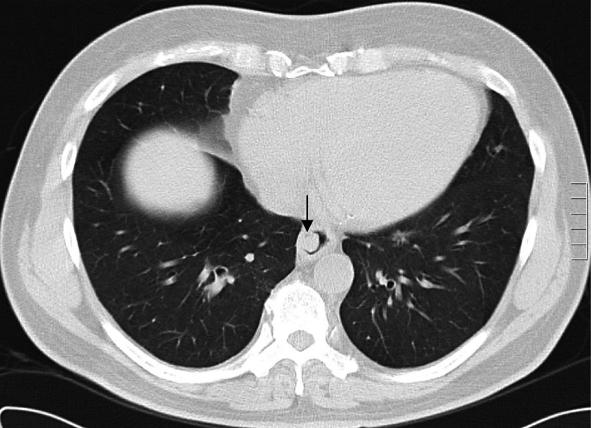

Metastasis to the oesophagus is most frequently described in association with lung or breast cancer. Diagnosis is frequently complicated as often only normal tissue is present in endoscopic biopsy specimens. Although oesophagectomy for metastasis has been described, few patients are suitable for curative resection. We report the case of a 62-year-old man who developed an oesophageal metastasis from colorectal cancer and review the available literature.

食管癌转移最常被描述为与肺癌或乳腺癌相关。诊断常常很复杂,因为在内镜活检标本中通常仅存在正常组织。尽管已经报道了针对转移灶的食管切除术,但很少有患者适合进行根治性切除。我们报告了一例62岁男性发生结直肠癌食管转移的病例,并对现有文献进行了综述。